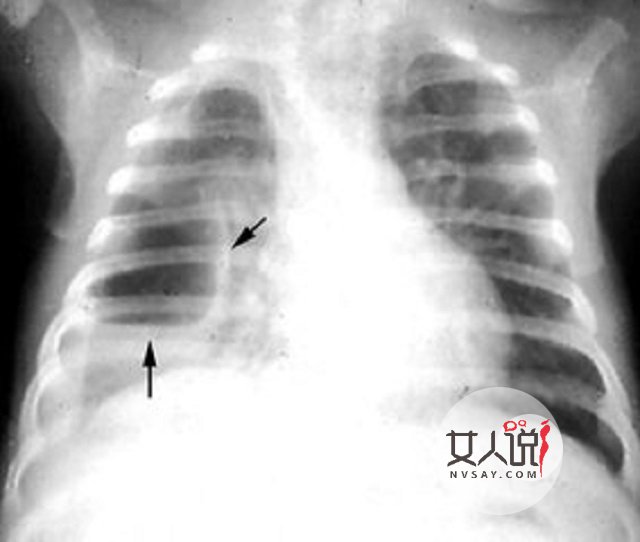

脓胸 高热不退;呼吸困难加重;患侧呼吸运动受限;语颤减弱;叩诊呈浊音;听诊呼吸音减弱,其上方有时可听到管型呼吸音。当积脓较多时,患侧肋间隙饱满,纵隔和气管向健侧移位。胸部X线示患侧肋膈角变顿,或呈反抛物线状阴影。胸腔穿刺可抽出脓液。 小儿支气管肺炎 脓气胸 肺脏边缘的脓肿破裂并与肺泡或小支气管相通即造成脓气胸。表现为突然呼吸困难加剧,剧烈咳嗽、烦躁不安、面色发绀。胸部叩诊积液上方呈鼓音,听诊呼吸音减弱或消失。